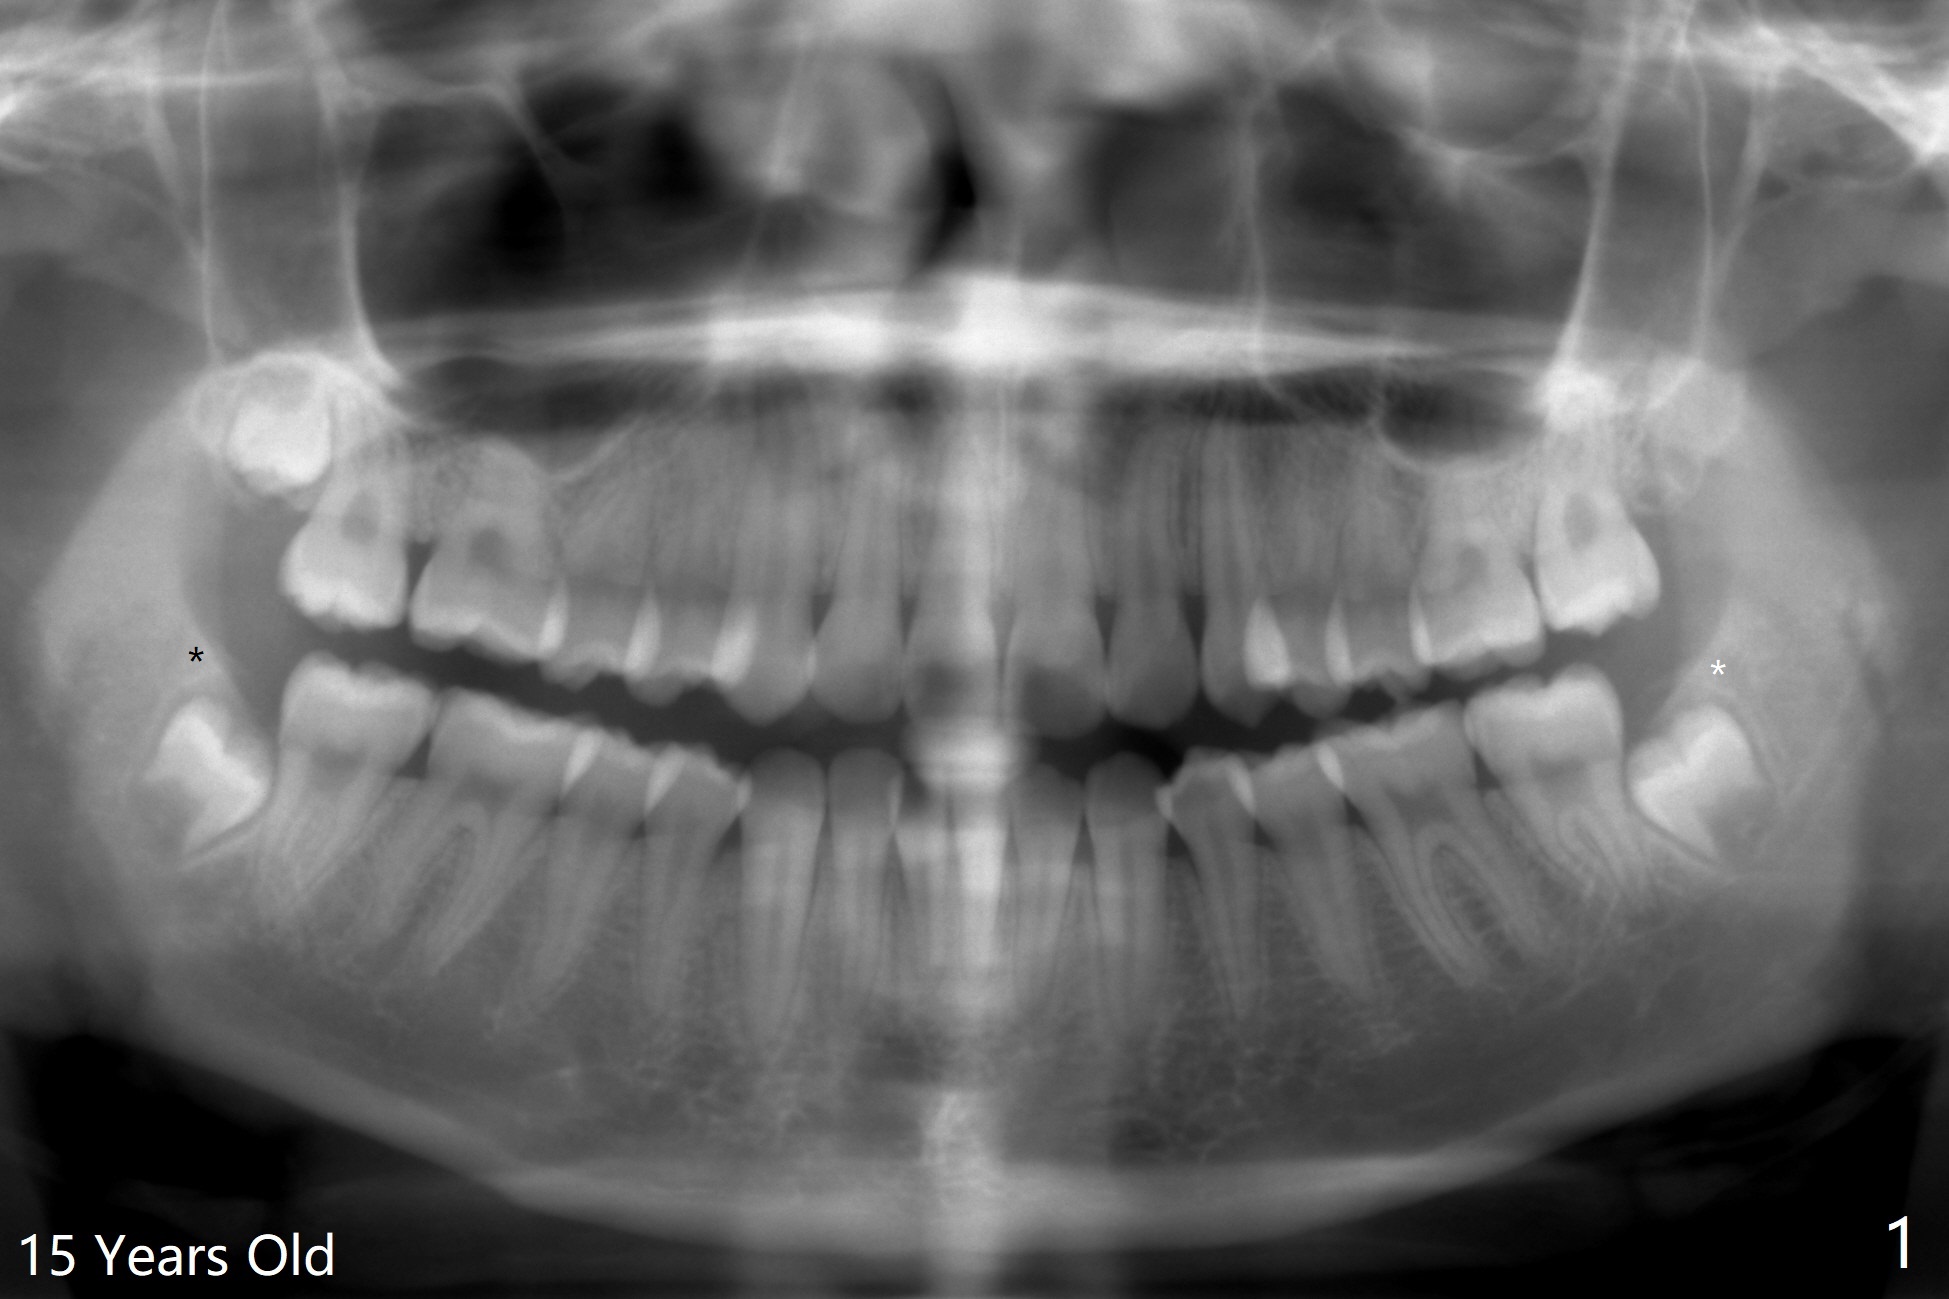

15岁女孩外斜嵴好像小三角形,骨质密度低(图一),18岁时三角形变大,密度增高(图二)。术前拍摄小范围CT,术中切开后,拍摄照片显示外斜嵴,随着颊侧去骨,嵴被破坏(拍照)。